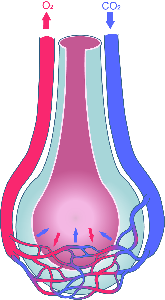

Detailreiche Fotografien aus der medizinischen Praxis ergänzen die Texte; moderne, genaue,

wissenschaftliche Zeichnungen geben Einblick in die Anatomie und die Funktion der Lunge und

anderer Organe.